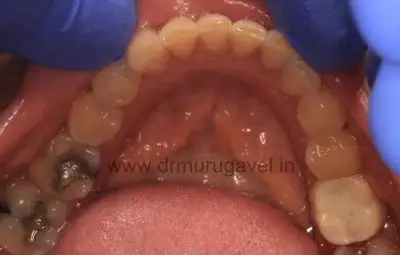

Before Treatment:

Upper Occlusal View